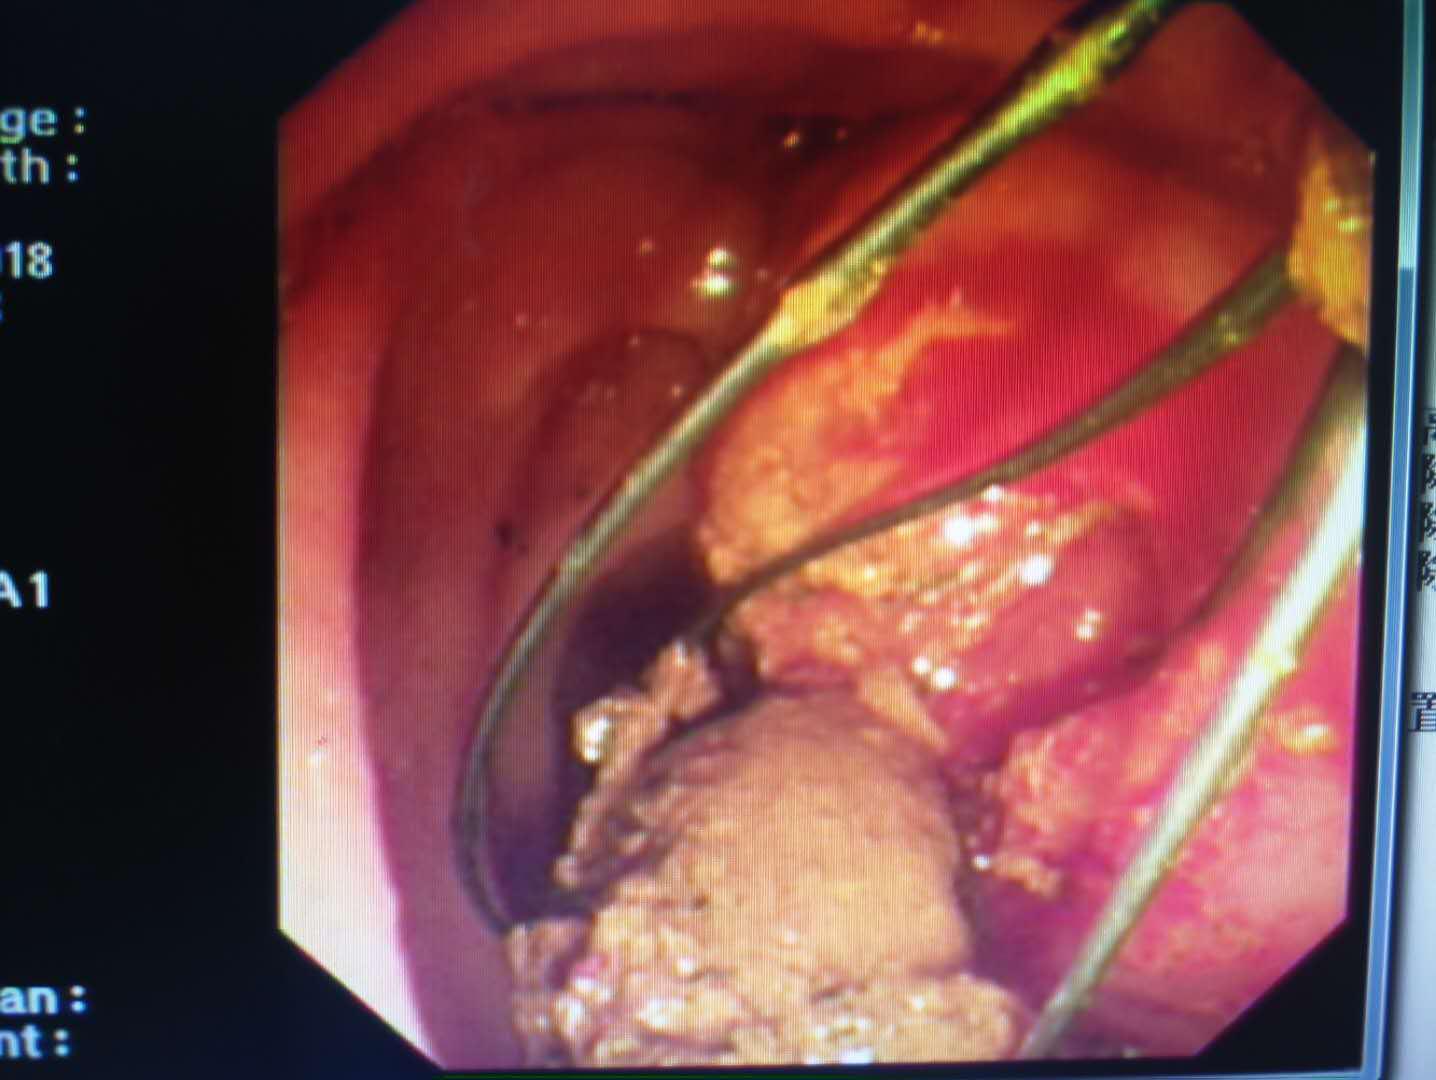

患者梁某,女性,87岁,因“腹痛2月”收住消化内科,诊断为胆总管结石、化脓性胆管炎、冠心病、心房纤颤、高血压2级、脑梗塞、电解质紊乱(低钾血症)。患者入院后伴有发热,最高体温41℃,急性化脓性胆管炎症状急剧加重,生命危在旦夕,一分一秒都在与生命赛跑。以往唯一生还的机会就是开刀手术,但是这位高龄患者很难下手术台;如果保守治疗唯一的结果就是因感染性休克及严重合并症而死亡。就在此时,消化内科主任王宇晖、主治医师曹鹏、白欣与手麻科雷育华主治医师、介入科何彤副主任多学科联合会诊,根据病情迅速制定了最佳手术方案,那就是为患者实行ERCP胆道取石。手麻科迅速为患者实行插管麻醉,密切监护生命体征,介入科配合,由曹鹏医生快速将胆管内的巨大结石顺利取出,迅速解除了胆道梗阻,缓解了患者胆道压力,安全有效缓解了患者的危重病情。